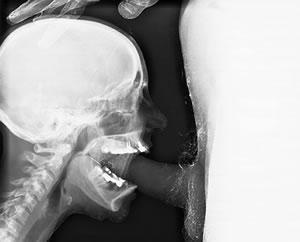

Test your skills at radiology...

Is that a real one or a bogus one ?

The shading of the greys are reversed. You can see tissue, including a penis on film. This image is just a crappy image and has been butchered. The more dense the bone is, the whiter it will appear on film. A human skull does not appear that dark. The teeth in the jaw look horrible on that image. There's no definition of the teeth on the maxillary (upper) right side, which either the person moved and blurred the image, or the image was doctored. If the person moved, the lower right teeth would be blurred also. They aren't. There's a bridge on the lower right side replacing the 2 missing premolars, but there is no real definition of the canine or other lower anterior teeth. The roots and pins are not correct shades of grey. The tongue is missing. Neck muscles do not appear like that on film. The details are all reversed on the film. You can see details of the fingers, parts of the jaw, but not on the penis?

Cephalometric, panoramic, x-rays do allow for you to see the nose, lips, and chin. On these films and periapicals, you can see nerves in individual teeth and the nerves in both jaws. If you can see the nerve paths in the jaw, you would also be able to see the nerves and blood supplies in the penis. The image has his penis as transparent and without detail.

Panky, I was thinking about a lot of those too. But what made me guess bogus was the guys pubic hair. Hair doesn't show up on screen. Oh and where are his bones? The "blower" is all bones and the "blowee" is all......non boney. Maybe, but I don't think so

I don't really know, but methink its a lot of photoshopping from real x-rays.

All of Panky's observations are real, however, the image being in negative from regular x-ray means very little.

To obtain imaging of the flesh, you need low energy. A mamograph, IIRC, runs at around 40KVolts of energy or less.

At low energy, you'd see finger bones as big blocking objects.

You barely see the bones in the hand so the hand must have been taken at higher energy, so taht the rays punched through. But at high energy, you wouldn'd see the flesh. The trick ? Methink the guy dipped his hand in baryum. That explain why you see the fingernails and the cuticle areas as blocked, standing out. Otherwise, you'd see only bones. Still, this is unsatisfactory as an explanation because you'd see a blocked edge around the fingers if they had been dipped in baryum. They were probably wiped off afterward.

Radiopaque (baryum) was probably also rubbed lightly on pubic hair of the guy to appear that much, for there is no chance in hell you could get to see hair otherwise.

Methink that this pic is a composite of three or four images. The guy's dick at meduim energy with his pubic hair rubbed with baryum, the hand at high energy dipped in baryum, and the skull, possibly a superposition of high energy (bones only) and low energy shots flesh with skulls blocked out)

All that photoshoped into one.

And then, the image was reversed to become positive from the original x-rays negatives.

I agree that it is more than one image layered. It makes sense considering the inconsistencies of the details.

Feynman is right about the speed at which certain details are viewable.

I think with the pubic hair and the penis, it was an actual photograph, photoshopped to look like an x-ray image. Doctored image or negative and then combined that with an actual x-ray image of a skull. Maybe the same with the hand since no actual bone structure is visible.

Barium powder could've been used. Metallic powders...

Here is what the photo looks like with the grey scale inverted. Looks more like an actual x-ray. The image(s) are still not correct as far as detail is concerned.